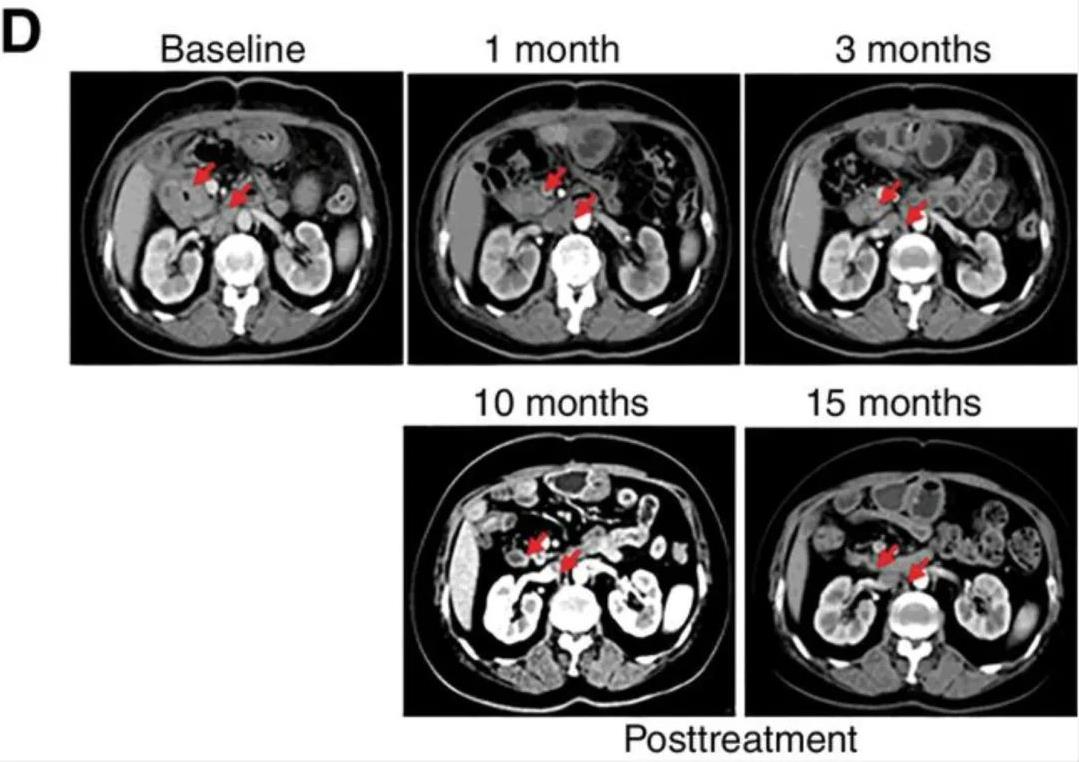

3、原发灶及转移灶消失:治疗后达到完全缓解(CR)的这名幸运患者,诊断为远端胆管癌(dCCA),且伴有腹膜后淋巴结转移。该患者在接受CART-EGFR细胞治疗后3个月达到完全缓解(CR),复查CT和PET/CT显示,代谢性原发性肿瘤病灶、转移性腹膜后淋巴结消失(详见下图)。该患者的PFS持续长达22个月以上。

图1 患者在CART-RGFR细胞治疗前,治疗后1、3、10和15个月的CT图像对比

▲图源“AACR”,版权归原作者所有,如无意中侵犯了知识产权,请联系我们删除

注:红色箭头表示:原发性肿瘤和腹膜后淋巴结转移。